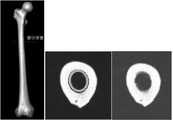

도 33은 상기 대퇴골의 길이를 따라 상기 대퇴골 중앙의 관(canal) 허리 및 대퇴골 허리를 나타내는 대퇴골의 3D 모델이다.

FIG. 33 is a 3D model of the femur showing the canal and femoral center of the femur along the length of the femur.